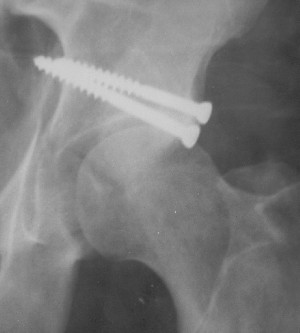

Послеоперационный снимок прямой 5/05/03

Больной 18 мая 2003 года в автоаварии получил перелом левой вертлужной впадины, вывих бедра. Госпитализирован в один из стационаров области.Вывих вправлен. В последствии бедро вывихивалось еще дважды. На консультацию был представлен снимок от 19.05.03г., больной переведен к нам 3.06.03г. Снимок при поступлении - перелом впадины, задне-верхний вывих бедра. 05.06.2003 г. выполнено открытое вправление вывиха левого бедра и остеосинтез стенки вертлужной впадины двумя винтами. Послеоперационный период без осложнений. Объем движений в левом тазобедренном суставе восстановился полностью. Выписан на амбулаторное лечение в удовлетворительном состоянии с рекомендациями 3 месяца ходить на костылях без нагрузки на оперированную конечность. На контрольных рентгенограммах левого тазобедренного сустава 13.10.2003 г. - признаки консолидации перелома; плотность, форма головки и состояние суставных поверхностей удовлетворительные. Разрешена дозированная осевая нагрузка, на конечность с использованием дополнительной опоры. 19.12.2003 г. больной обратился с жалобами на боли в левом тазобедренном суставе. На рентгенограммах левого тазобедренного сустава 19.12.2003 г., 20.02.04г. - асептичекий некроз головки бедра. 5.04.04г. - эндопротез. Сейчас ходит без трости, не хромает. Особенность эндопротезирования - при удалении винтов прослежена линия перелома заднего края впадины и предложено установить чашку несколько меньшего диаметра, чтобы она была покрыта несломанной частью.